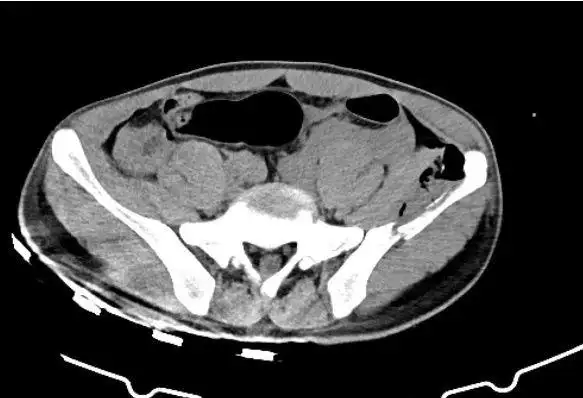

自发性肾破裂的急诊介入超选择栓塞

胸部ct97肝脏,脾脏密度不均,怀疑破裂97左肺,左肾挫裂伤97左侧